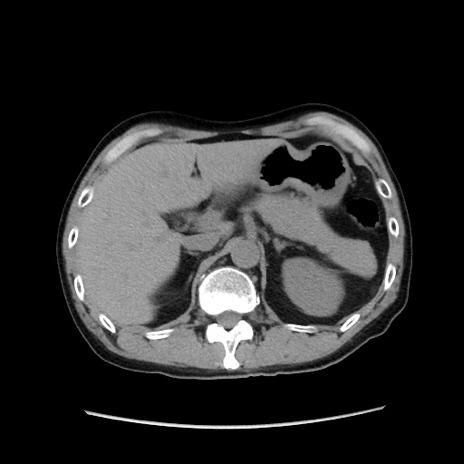

冠状断像

【症例】40歳代 男性

【主訴】腹痛

【現病歴】4時間ほど前に電車に乗車中に臍部上より腹痛出現。徐々に増悪し起立困難となり、救急外来受診。生ものは数日食べていない。今朝お雑煮を食べた。

【身体所見】BT 36.8℃、BP 117/84mmHg、HR 91/min、SpO2 97%、苦悶様、腹部:臍上部広範囲圧痛あり、反跳痛±

【データ】WBC 8100、CRP 0.03